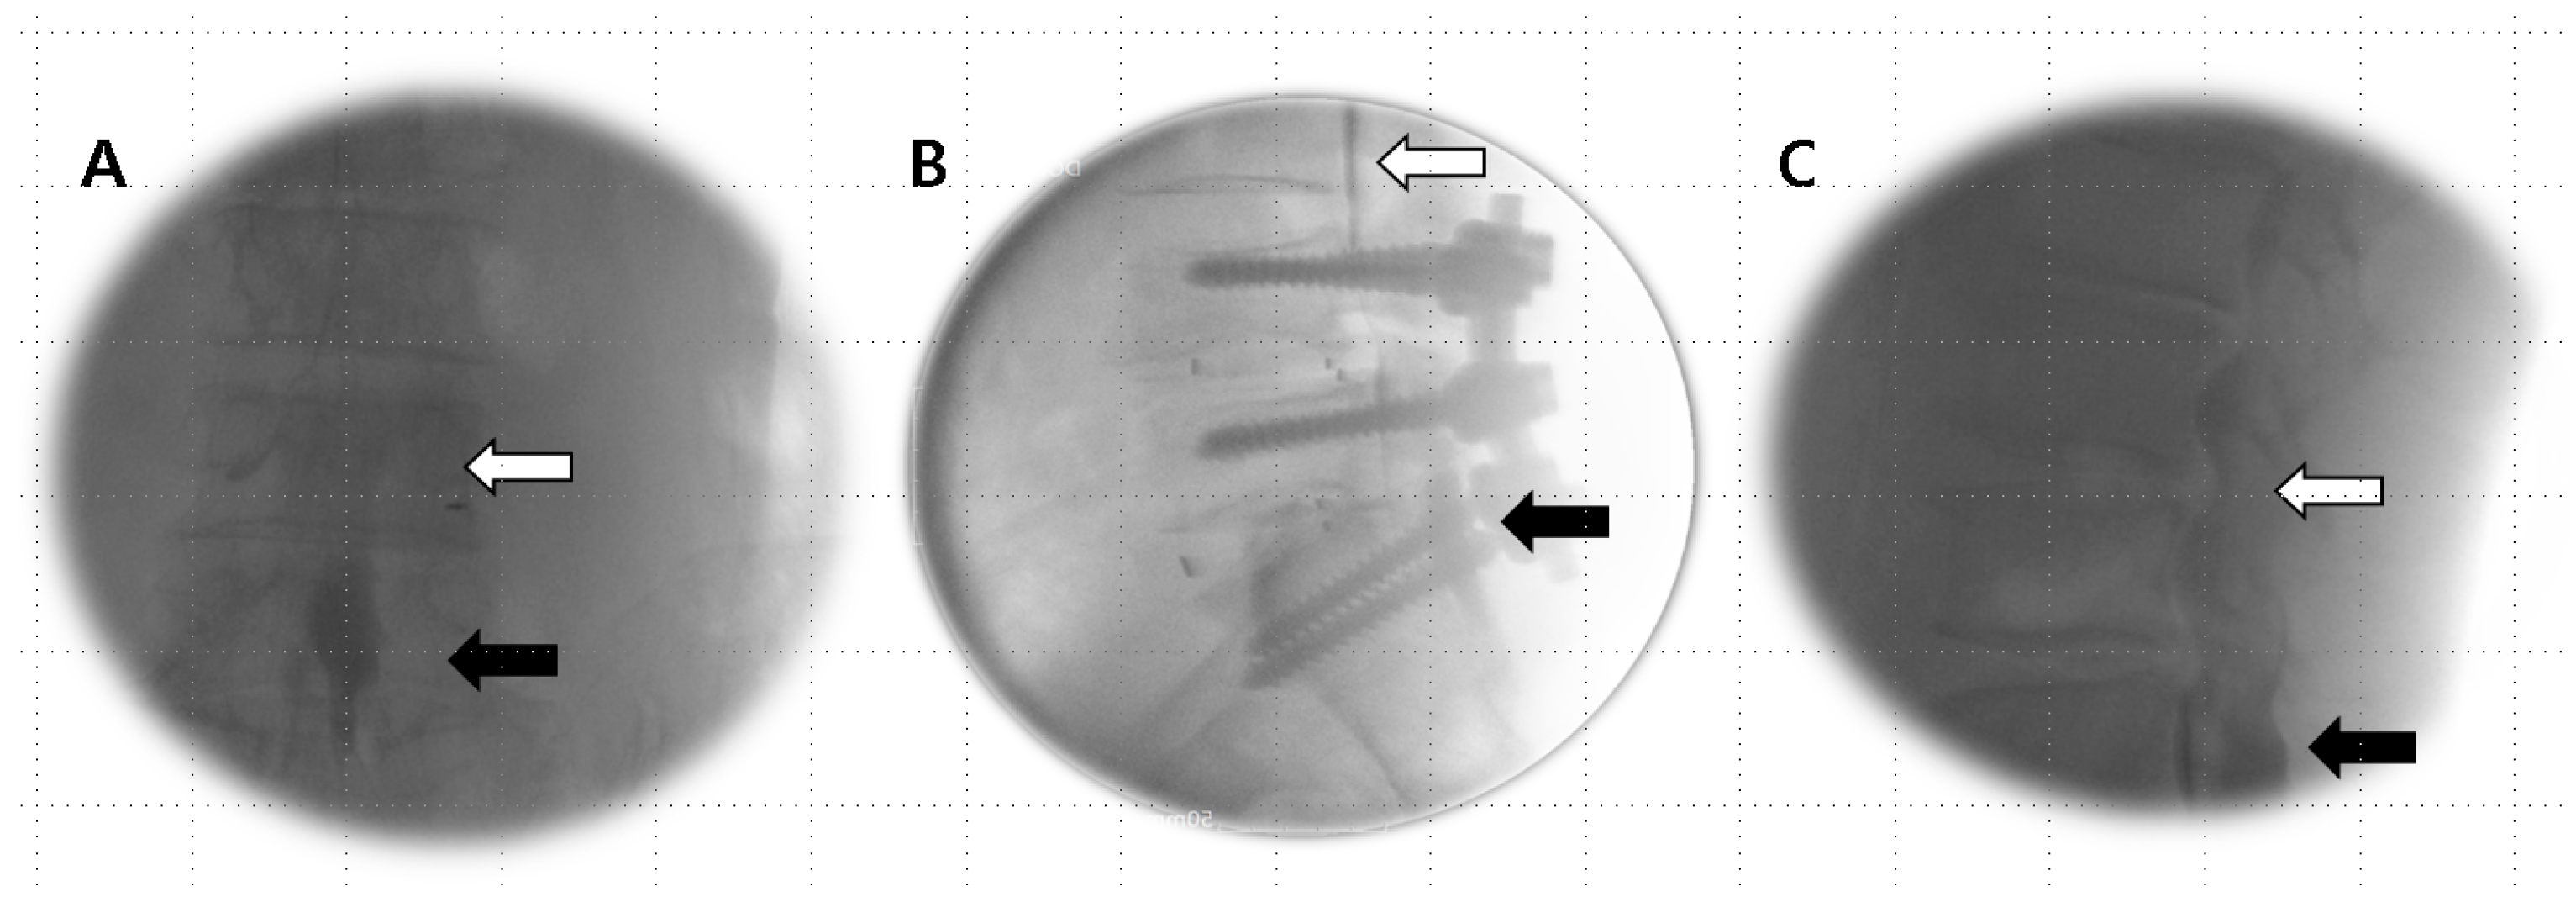

Anesthetics were administered if the Tuohy needle tip was situated within the epidural or subdural space (Figure 1A,B) or straddled between both spaces (Figure 2A,B).

Figure 2.

Combined epidural–subdural image. (A) AP view: imaging shows a thick, sausage-like mass of subdural contrast that transitions into a less dense epidural radiopaque image along the exiting nerve root, with the flow observed moving cranially. (B) Lateral view: the imaging reveals a progression from two thickened anterior–posterior columns positioned medially in the lower region (black arrow), transitioning to thinner, more peripheral anterior–posterior tracts (open arrow) that become more apparent in the epidural image as they flow cranially.